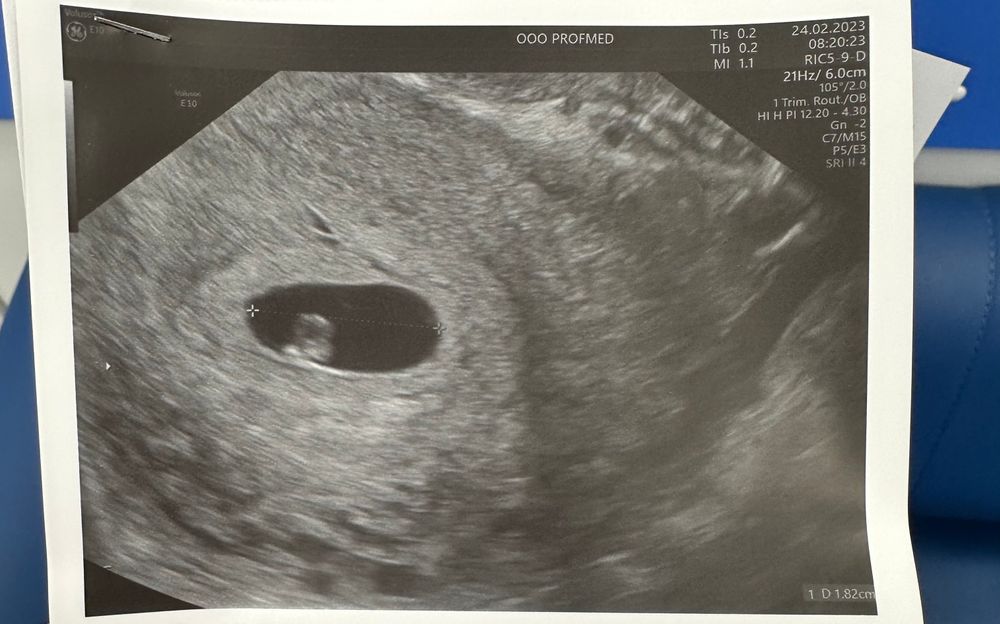

Мама девочки (4 года), жду мальчика, 10 неделя Москва

Метод Рамзи, просто любопытство))

Мне всегда было интересно где на этих снимках право а где лево)))

Художница со стажем, если вагинально узи то так и есть слева лево)) а если по животу то наоборот

Алиса, в данном случае получается слева же?) все тоже никак не пойму)

Елена Игоревна, да, все верно))

У меня было почти такое же расположение - мальчик в итоге) но не знаю, насколько это работает для всех детей😁

У меня такое расположение было- девочка! По Рамзи не сошлось!…🌸

У меня такое расположение на мальчика было